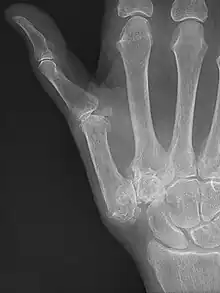

Osteoarthritis of the trapeziometacarpal joint

Showing the bones of the hand